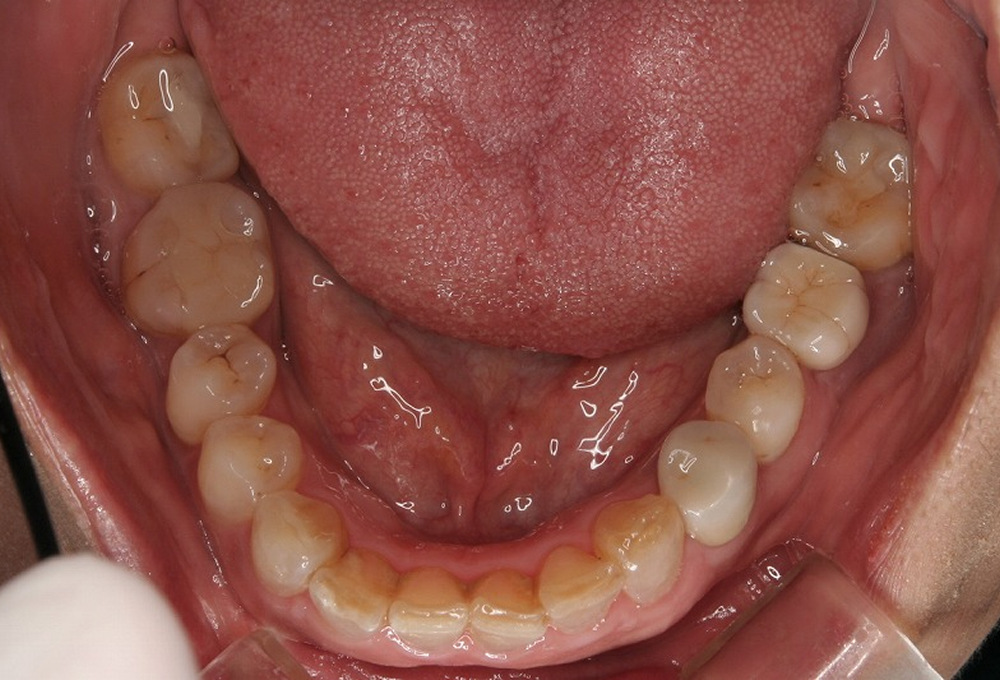

③術前下顎